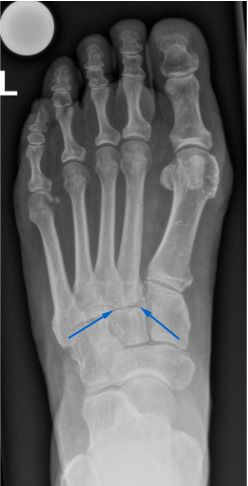

Röntgenbilder sind zur Diagnosestellung hilfreich. Zum einen zeigen sie meist bereits die Arthrose der Gelenke, zum anderen kann ihre Stabilität beurteilt werden. Aufgrund der Form des Fussgewölbes sind Röntgenbilder mehrerer Ebenen notwendig, um eine zuverlässige Aussage treffen zu können. Unter Umständen ist zusätzlich eine Magnetresonanztomographie (MRT bzw. engl. MRI für magnetic resonance imaging) nötig, um das genaue Ausmass der Arthrose und Verletzung des Mittelfusses bestimmen zu können.

Die Mittelfussarthrose kann nach einer Verletzung (posttraumatisch) oder durch Verschleiss (degenerativ) entstehen. Bei einer Verletzung des Mittelfusses können die Gelenke oder die Bänder, die für ihre Stabilität sorgen, geschädigt werden. Dadurch werden die Gelenke falsch belastet und es kann mit der Zeit zu einem frühzeitigen Verschleiss (Arthrose) kommen. Eine Fehlbelastung aufgrund einer Fehlstellung, z. B. bei einem Knicksenkfuss, kann ebenfalls die Arthrose begünstigen. Weitere Ursachen sind rheumatologische oder neurologische Erkrankungen oder eine Überlastung nach einer Rückfussversteifung.